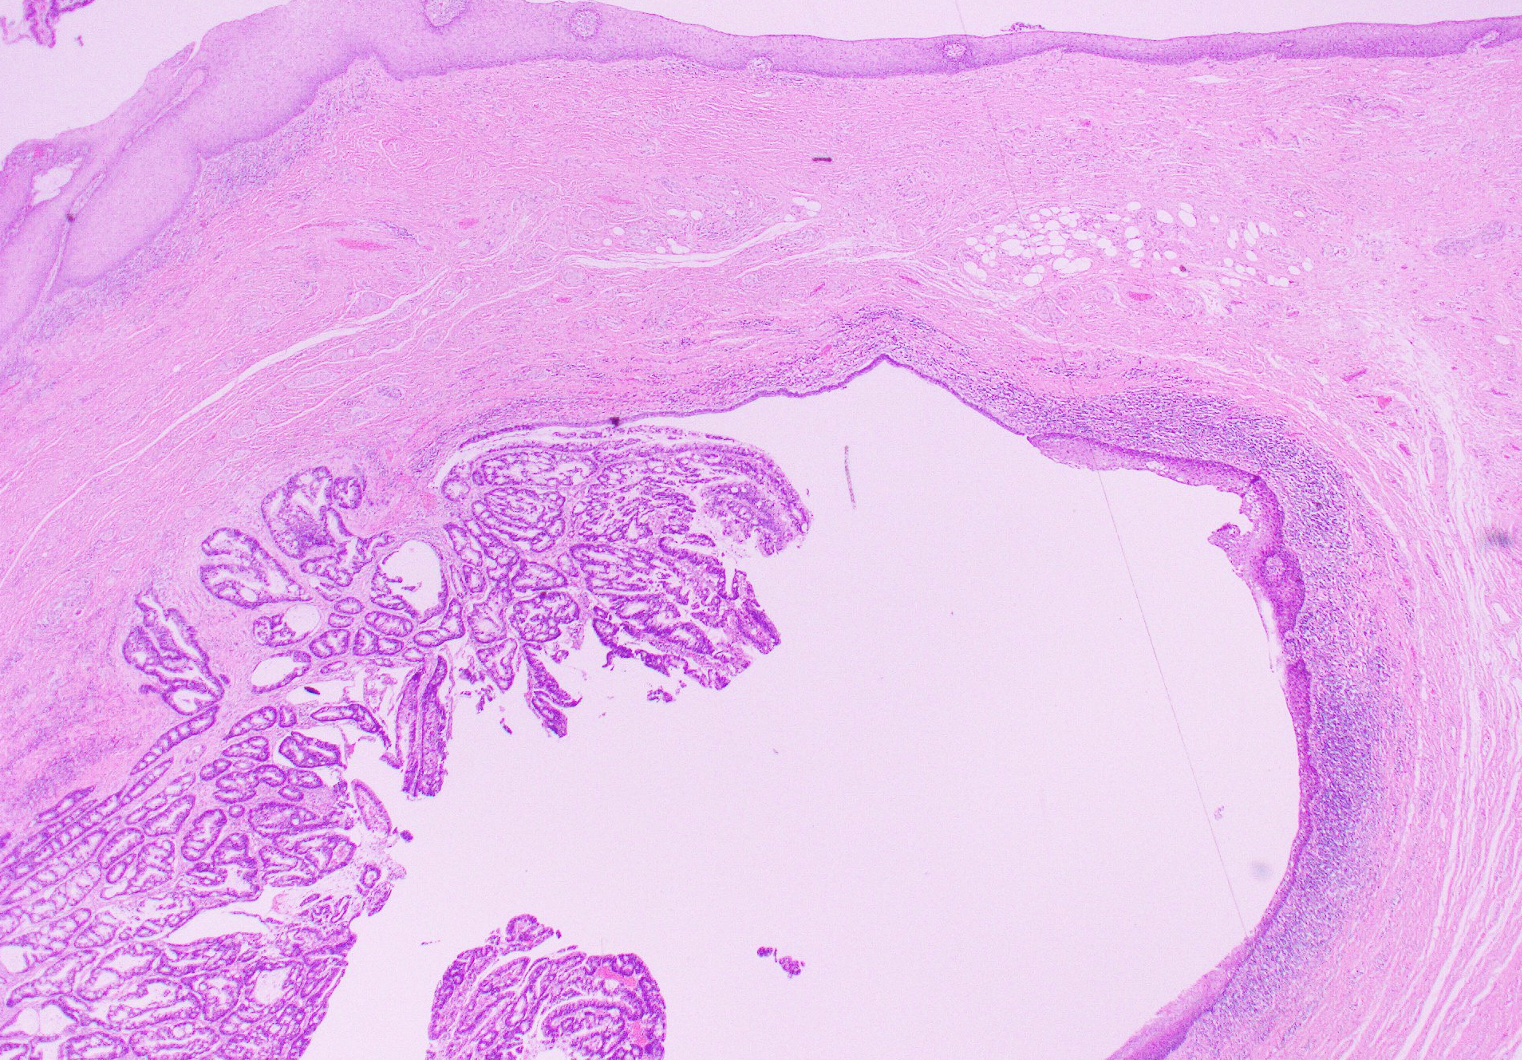

H&E micrograph showing adenocarcinoma (bottom left) arising from the mucosal lining of a pre-existing sinus tract. Overlying squamous mucosa (top) is benign.